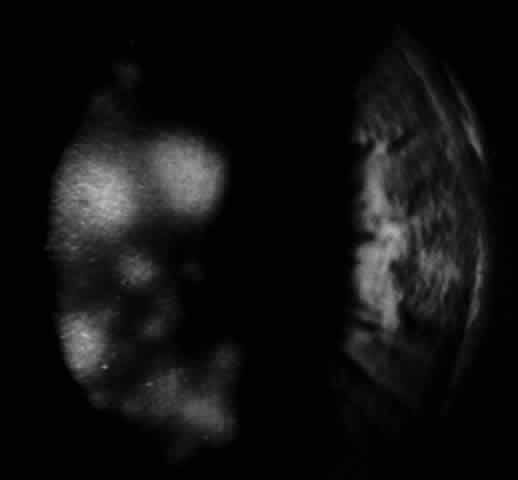

Reported studies using PCR to detect EBV genomes in normal and Sjögren's syndrome lacrimal gland biopsies did not indicate the infected cell types within the lacrimal gland, nor did they determine if the amplified EBV DNA sequences were from latent EBV genomes or replicating virus. The results of studies reported by Pflugfelder and associates82,83 suggest that EBV may persist in the normal human lacrimal gland in a latent nonpathologic state. The cellular site and state of genome expression in normal human lacrimal glands persistently infected with EBV appears to be similar to that reported to occur in normal salivary glands (Fig. 6).25 In contrast, the results of studies using in situ DNA hybridization and immunohistochemical techniques to evaluate Sjögren's syndrome lacrimal glands for EBV infection indicate that there may be a much more extensive infection of ductal epithelia than observed in normal lacrimal glands, as well as infection of mononuclear cells in areas of B-cell lymphoproliferation. EBV antigens were detected in both lymphocytes and epithelial cells in Sjögren's syndrome lacrimal glands; however, the pattern of antigen expression differs in these two cell types. EBV antigens associated with immortalization of B cells, LMP-1, and EBNA-2 were detected in mononuclear cells in areas of B-cell lymphoproliferation. B cells in Sjögren's syndrome lacrimal glands expressing EBV latent infection cycle antigens also expressed ICAM-1, CD-23 and CD-21, the typical repertoire of antigens upregulated by EBV following immortalization of B cells. Based on these findings, it appears that EBV infection of B lymphocytes in Sjögren's syndrome lacrimal glands may be responsible for the B-cell lymphoproliferation observed in these glands. In contrast, epithelial cells located in areas of lymphoproliferation in Sjögren's syndrome lacrimal gland strongly expressed early (EA-R) and late (VCA) EBV lytic-cycle antigens. These findings suggest that a lytic EBV infection may occur in epithelial cells in Sjögren's syndrome lacrimal glands. Because EBV genomes have been detected in the majority (80%) of tear specimens obtained from primary Sjögren's syndrome patients, it is possible that EBV-infected ductal epithelium may be the source of the virus shed into the tears. Similar to other EBV-associated neoplasias, a lymphoepithelial pathology is frequently observed in Sjögren's syndrome lacrimal gland biopsies.83 The lymphoepithelial pathology in Sjögren's syndrome lacrimal glands differs from nasopharyngeal carcinoma in that lymphoproliferation surrounding epithelium in Sjögren's syndrome lacrimal glands consists predominantly of B lymphocytes, whereas T cells typically surround epithelia in nasopharyngeal carcinoma.84 In lacrimal gland lobules with mild inflammation occurring in patients with Sjögren's syndrome, the B-cell lymphoproliferation is observed surrounding ducts in the center of the lobule and normal-appearing acini may still be present in the peripheral lobule. In more severely affected glands, the lymphoproliferation replaces all secretory acini and the ducts in areas of B-cell lymphoproliferation have an abnormal morphology and pattern of cytokeratin expression.83

Fig. 6. A. Normal lacrimal gland biopsy showing hybridization signals for EBV DNA in intralobular duct epithelia indicated by black arrow (X 100 original magnification). B. Magnified photomicrograph of EBV-positive ductal epithelia in upper figure (X 400 original magnification).